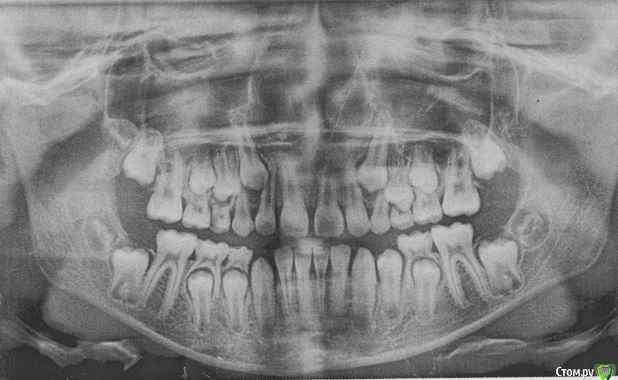

Мама пациента Опубликовано 20 мая, 2016 Поделиться Опубликовано 20 мая, 2016 Письмо на форум стоматологов. Здравствуйте, уважаемые доктора. Извините за много букв, но короче не расскажешь. Дочери 12 лет. Никогда не замечала перекрёстного прикуса, вдруг в июне 2015 г. на регулярном осмотре терапевт сказала, что прикус перекрестный, нужно срочно бежать к ортодонту, а то ребенок «съест» зубы, хотя раньше не говорили об этом. Видимо поспешили с выбором врача. Доктор хорошая, старательная, молодая, но видимо у нас не совсем линейная ситуация, с которой раньше она не сталкивалась. Здоровье, к сожалению, у ребенка не богатырское, парез лицевого нерва был с рождения, дисплазия соединительной ткани – исследованиями не подтвержденная (много гибкости, мало силы и упругости мышц). Поставили брекеты на верхние зубы в июле 2015- 11 лет. Нижнюю челюсть наклеили в ноябре. ОПГ снимок до того прилагается. Кроме него исследований не делали, теперь поняла, что надо было. Все поездки к врачу заканчиваются 3-х-5-ти дневными страданиями. В марте после поездки (наклеили клыки, прорезающиеся нижние 7-ки и поменяли дуги), на следующий день поднялась тем-ра 37,7 и потом 3 недели!!! она была субфебрильная. Анализы крови и м. были нормальные (немного снижены сегментоядерные и повышены лимфоциты). Это сопровождалось головокружением. Лечили синусит. По ВСД по назначению невропатолога сделали исследования (ЭЭГ, УЗДГ- ТГ)- повышено внутричерепное давление (результаты есть). Сделали 4 сеанса у мануального тер., который по его словам «снял блок с шеи…и сделал спину (убрал начинающийся сколиоз)». Головокружения прекратились. Сходили на консультации к хорошим ортодонтам в Москве, к сожалению, никто пока помочь не берется. После одной из консультаций (врач достаточно активно двигала челюсть) опять кружилась голова в течении пары часов. На консультации к челюсно-лицевым хирургам пока не попали, т.к. в Москве к гуру целая история попасть, а конец учебного года и два пропущеннных месяца в школе. Но операцию делать я ей не буду, т.к. риски для здоровья от операции гораздо выше. Будет взрослая сама решит. Случай не простой, время упущено, челюсть выросла криво, но рост еще идет (доктор сказал по ренгену ладони). Неужели в стране нет специалиста, который в комплексе занимается ортодонтией с содружестве в неврологами и мануальными (краниальными) терапевтами. Может кто-то занимается миотерапией (лечебная физкультура для челюстей). Сейчас просто боимся идти к ортодонту менять дуги и доклеивать отвалившиеся брекеты и я, и ребенок. Потому, что 4 недели мучений и по учебе уже пропустили пол-четверти. Ей хочется все бросить, оторвать все брекеты и забыть, как страшный сон. Хотя я прекрасно понимаю, что таким прикус оставлять нельзя, надо попытаться что-то сделать. Что бы вы делали для своего ребенка в этой ситуации? Ссылка на комментарий

Yana guapa Опубликовано 20 мая, 2016 Поделиться Опубликовано 20 мая, 2016 при перекрестном прикусе я бы не ставила брекеты на нижнюю челюсть. Потому что дуга дает расширение (а у вас итак нижняя челюсть больше верхней) если и ставлю брекеты на нижнюю челюсть, то на верхнюю челюсть изнутри (с небной стороны) ставятся кнопки, и пациент носит косые эластики (плюс все зубы должны быть разобщены на накусочных площадках, иначе они никогда не смогут "перепрыгнуть" через бугорки нижних) у вас такого разобщения не вижу, верхние зубы упираются в нижние. здесь хоть кучу дуг поменяй, но все будет стоять на месте. ортодонты, занимающиеся в содружестве с мануальными терапевтами, неврологами И так далее - на каждом углу. только вот результаты..... причина ваших головокружений так и не выяснена? когда нибудь были такие головокружения до постановки брекетов? Ссылка на комментарий